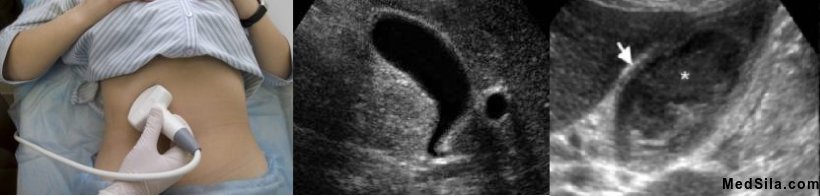

• УЗИ органов брюшной полости, которое является золотым стандартом диагностики холециститов. При данном исследовании можно обнаружить особенности строения пузыря и протоков, увеличение толщины стенок пузыря, их расслоение, наличие или отсутствие камней в пузыре и протоках, распространенность процесса, а именно не вовлечена ли в воспаление околопузырная клетчатка, состояние соседних органов и многое другое, важное для постановки диагноза и определения тактики дальнейшего лечения.

УЗИ желчного пузыря, норма и утолщение стенок, характерное для воспаления желчного пузыря.